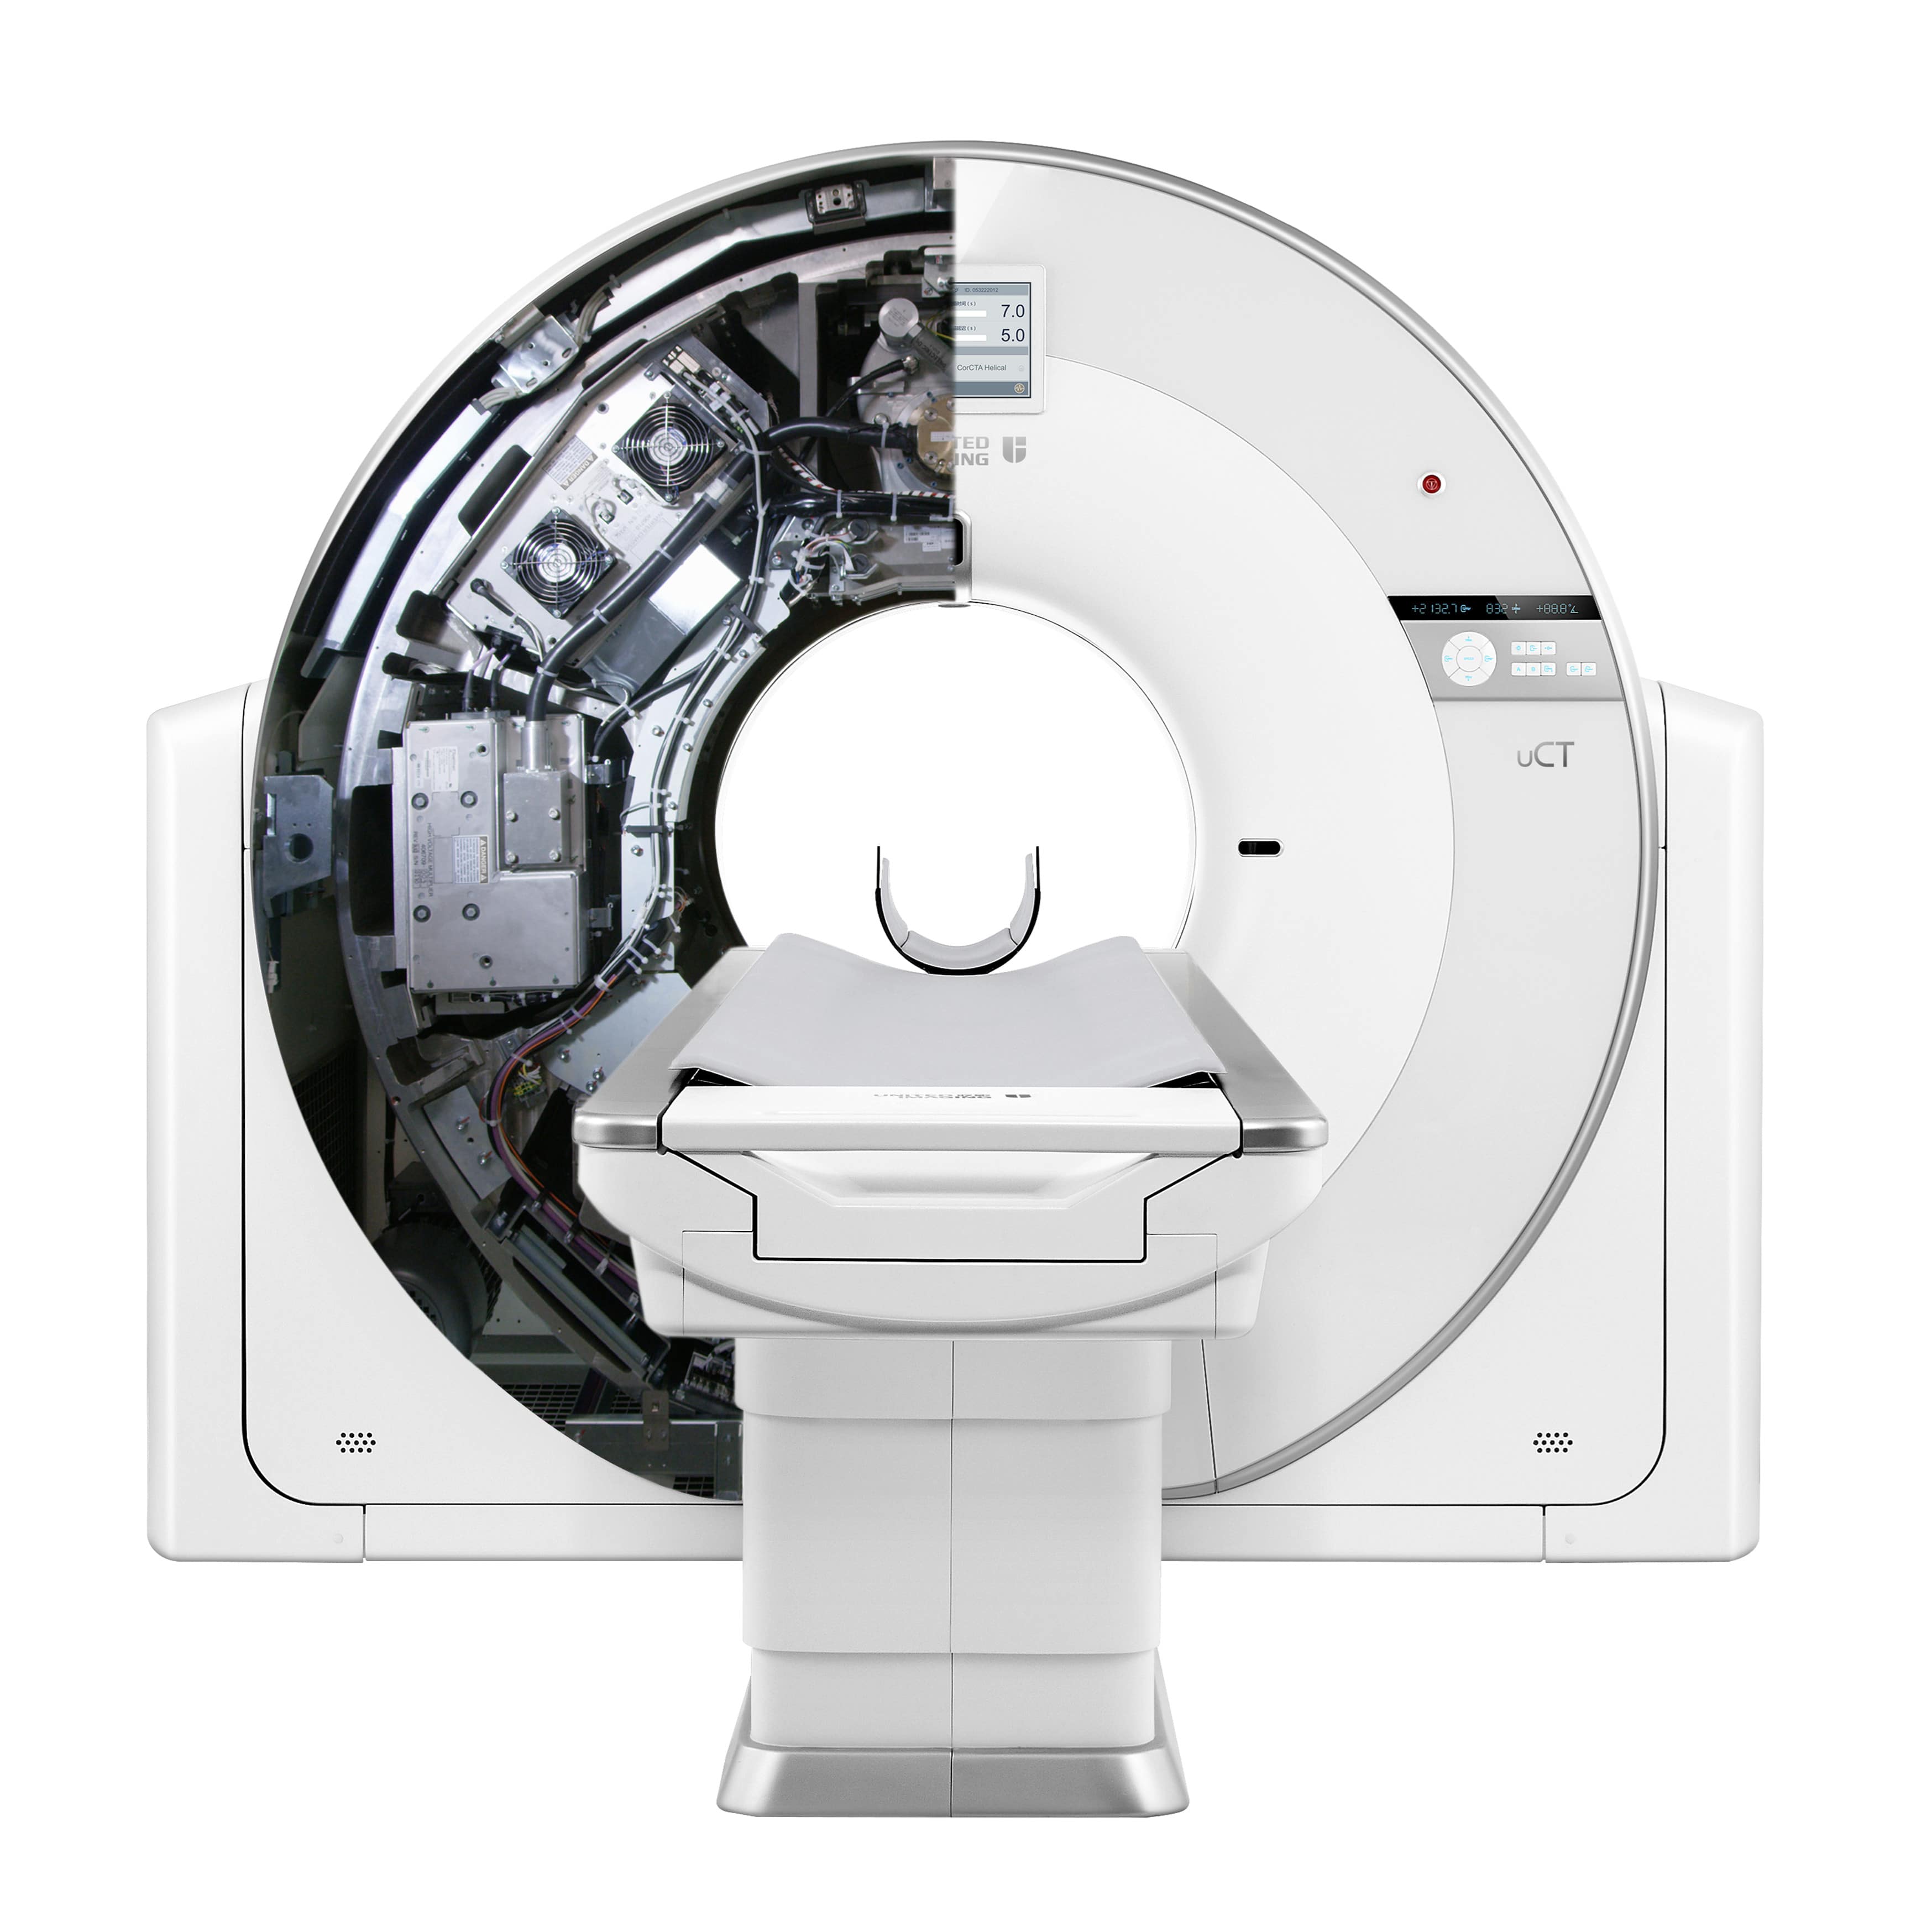

高端硬件

5.3MHU

大热容量球管,轻松应对高通量检查

50kW

大功率高压发生器,带来源源不断的澎湃动力

40排时空探测器

22mm覆盖,0.55mm层厚,卓越空间分辨率与密度分辨率兼而得之

70kV扫描模式

大幅降低辐射剂量,提高造影剂对比度,使微小病变等临床应用难点被突破